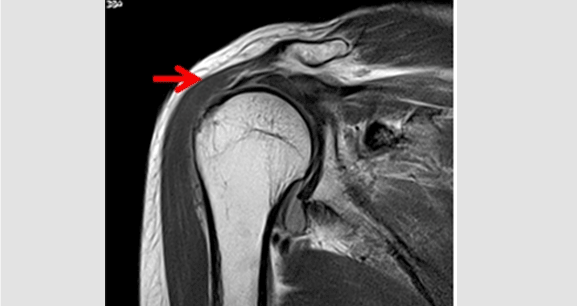

회전근개파열은 파열 된 정도에 따라 치료 방법의 차이가 있습니다. 부분파열의 초기 단계에서는 수술적인 치료 보다는 보존적 치료인 약물치료와 재활치료를 주로 시행 하며 중기 이상의 파열이 진행된 경우 수술적 방법을 시행 합니다.

회전근개파열 수술은 피부를 절개하지 않고 5mm정도의 몇 개 구멍만을 뚫어 봉합하는 관절경 수술입니다. 따라서 관절경 수술은 미용적 효과도 뛰어 날 뿐 아니라 정상조직 손상이 적어 빠른 회복 및 일상 복귀가 가능합니다.

회전근개 : 어깨를 움직일 수 있게 해 주는 주요 인대로 극상건, 극하건, 견갑하건, 소원건으로 구성되어 있으며, 이들 인대가 파열 된 질환을 회전근개파열이라고 합니다. 나이가 들어감에 따라 회전근개에 퇴행성변화가 생기며 이로 인해 회전근개파열이 잘 발생되게 되는데 흔히 50대 이후부터 시작합니다.

<파열된 회전근개>

<파열된 회전근개(MRI)>

<봉합된 회전근개>